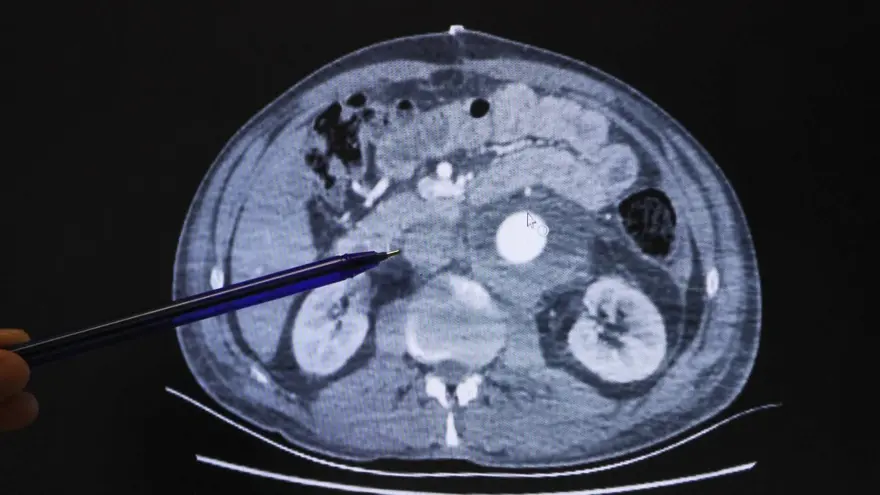

Kenger yine durumu önemsemedi. Ertesi gün ablası doktora gidip gitmediğini sormak için aradığında "15 günden önce randevu bulamam nasılsa" diye düşünerek MHRS'ye girdi. Tesadüfen 1 saat sonrasına randevu olduğunu gören Kenger, doktora gittiğinde gerçek ortaya çıktı. Karın bölgesindeki aort damarının çapı normalin 4 katına ulaşmış, yırtılma riski vardı. Üstelik genişleyen damar, böbreklerini de tehdit ediyordu.

"Kız kardeşim doktora gidip gitmediğimi sordu. Ben de randevu bulamam, en az 15 gün sonrasına verirler dedim. O anda telefon elimdeydi MHRS'ye girdim. Tesadüfen 1 saat sonra dahiliyede randevu buldum. Hemen gittim. Doktor EKO çektirdi. EKO muayenesini yapan doktor, 'Sizin kalp damar cerrahisine görünmeniz lazım' dedi. Saat 16.30, mesai bitmek üzere. Kalp damar cerrahı çıkmadan görüştüm. BT çektir dedi. Şansımdan herhalde, çok kısa zamanda bunlar gelişti. 'BT riskli duruyor. Böbrekler riska altında. Bizim uzmanlık alanımızı aşıyor' dedi. İlk söyledikleri isim, İstanbul'daki Mehmet Akif Ersoy Hastanesi oldu. 8 santimlik bir anevrizmanın vücudumda olması ve benim o şekilde hayatta kalabilmem, masör arkadaşın bunu tesadüfen fark etmesi benim hayatımı kurtardı. Gerçekten de mucize gibi bir şey oldu."